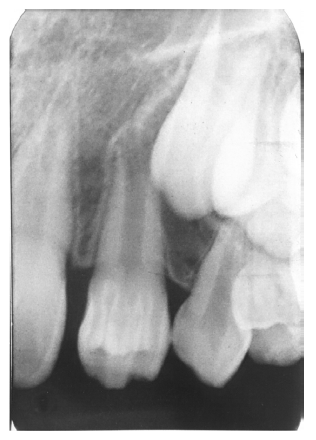

Dentin caries extends into the tooth dentin and can be recognized by noting the focal loss of dentinal radiopacity. Most commonly, this darkened dentin is located beneath carious enamel and, typically, the lateral dimension of the dentinal involvement exceeds that of the associated enamel caries (Figure 3). Dentin caries may be discerned interproximally, on the occlusal surface, buccally/lingually, or on root surfaces.

Figure 3 - Dentin Caries

Figure 3